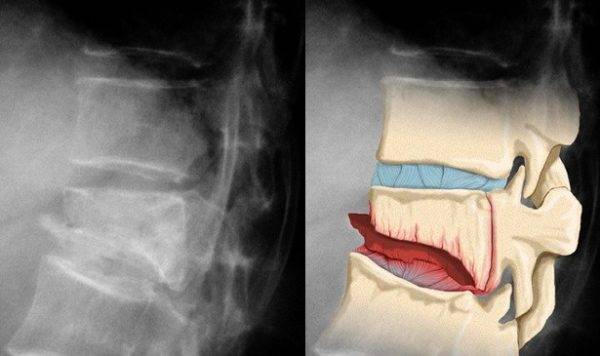

Но неудачный или резкий наклон, поворот, поднятие тяжелой сумки или резкий рывок провоцируют выпадение поврежденного фрагмента позвонка, приводя к травме острыми краями окружающих артерий, нервов, а также спинного мозга.

В этот момент перелом становится заметен визуально, появляется неестественный изгиб позвоночника.

Скажем, если со временем нарушение чувствительности приобретает более тяжелую форму и сопровождается патологией, которая затрагивает движение, то чаще всего в данном случае имеет место компрессия спинного мозга, вызвать которую может и гематома, и части костей, и смещенный позвонок, а также частицы связок